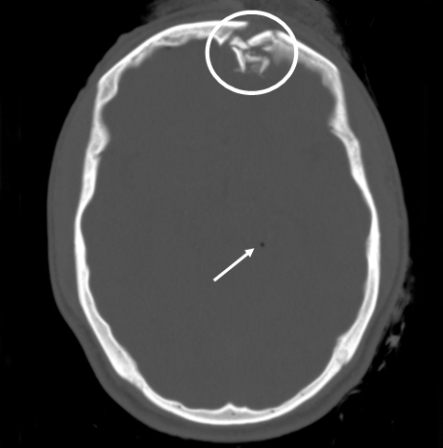

Coronal CT of an open, comminuted, depressed skull fracture. The level of depression is greater than the bony table and there are several bone fragments impacted below the inner cortex of the opposing bone (large arrow). Despite lack of underlying associated brain injury this fracture required operative debridement and elevation of the bone fragments. See also the corresponding sagittal CT image

From the teaching collection of Demetrios Demetriades; used with permission

Sagittal CT images of an open, comminuted, depressed skull fracture. Note the associated pneumocephalus (small arrows). The level of depression is greater than the bony table and there are several bone fragments impacted below the inner cortex of the opposing bone (large arrow). Despite lack of underlying associated brain injury this fracture required operative debridement and elevation of the bone fragments. See also the corresponding coronal CT image